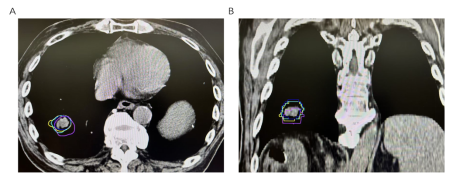

肺部与其他部位肿瘤存在的最重要的不同在于,肺部是一个不断运动的器官,随着我们的呼吸,肺部会不断地膨胀和收缩。这就意味着,肺部的肿瘤也会随之移动。如果不能准确地"看见"肿瘤的位置,很容易造成放疗时"打偏",既达不到治疗效果,还可能伤及周围的正常组织。所以肺部肿瘤放疗定位时,经常需要进行4D-CT扫描,它不仅能提供静态的图像,还能捕捉肿瘤随呼吸运动的轨迹。通过4D-CT,医生可以了解肿瘤在不同呼吸阶段的位置变化,从而根据患者独特的肺肿瘤呼吸运动情况,有针对性地制定个体化的放疗计划。如图1所示:不同颜色的曲线代表呼吸周期中不同时相下肺部肿瘤位置,从该图可以看出,呼吸运动过程中肺部肿瘤有较大的位置变化。制定放疗计划时不同呼吸时相肿瘤运动的范围要全部包括在放疗的照射范围内,这样就可以保证不管是吸气末还是呼吸末,肿瘤始终逃不出放射线的五指山。这个过程同样需要患者的配合,并且配合的程度直接决定了肿瘤放疗的效果以及正常肺损伤的损伤情况。试想一下,如果4D-CT扫描过程中,患者始终保持深呼吸,那肿瘤的移动范围必然增加,进一步的放疗的照射范围随之增加,这样正常组织出现损伤的概率必然增加。最严重的情况,定位时患者小幅度呼吸,放疗时因为紧张等变成了大口呼吸,那肿瘤将脱离我们设定好的照射范围,这样放疗后肿瘤很快就会进展。那最理想的状态是,放疗定位时稍微早到一会,熟悉环境和流程,不要紧张,定位开始后要小幅度的浅呼吸,这样肺肿瘤的运动幅度就相应减少。最重要的,放疗时要保持和定位时一致的浅呼吸,切记不可转为深呼吸,以免肿瘤逃出我们根据浅呼吸状态下制定的放疗照射范围。

图1:不同呼吸时相下肿瘤位置变化。